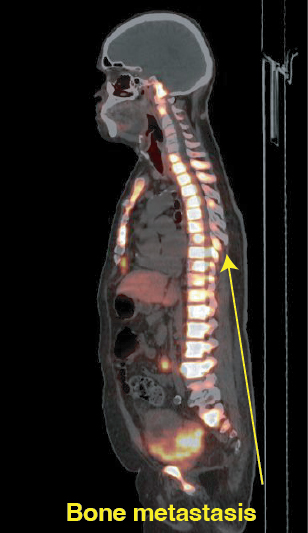

Precision imaging using advanced modalities such as PSMA PET-CT

Accurate identification of disease spread

Cancer widely spread to lungs, bones, and lymph nodes

Resolution of lung metastases

Significant reduction in bone lesions